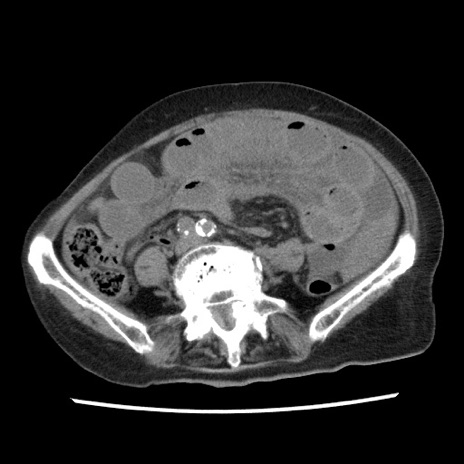

冠状断像

矢状断像

【症例】80歳代女性

【主訴】腹痛

【現病歴】8時間前から腹痛あり来院。

【既往歴】糖尿病、脂質異常症、子宮体癌にて子宮全摘術

【身体所見】意識清明・会話良好だが腹痛で苦悶様、全腹部にわたって反跳痛と圧痛あり

【データ】WBC 13600、CRP 0.14、LDH 224、CK 90